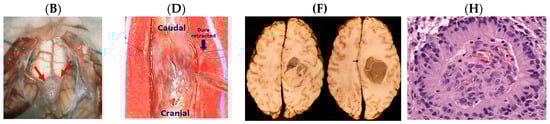

- Wikipedia. Oligodendroglioma. Available online: https://commons.wikimedia.org/wiki/File:Oligodendroglioma_001.jpg (accessed on 18 July 2017).

- Wikipedia. Glioma Gross 4. Available online: https://www.wikidoc.org/index.php/File:Glioma_Gross_4.jpg (accessed on 18 July 2017).

- World Health Organization Classification of Tumors. A Public Database of Human Cancers. Available online: http://www.pubcan.org/cancer/18/oligodendroglioma-nos/histopathology (accessed on 27 March 2017).

- Pathologyoutlines. CNS Tumor—Myxopapillary Ependymoma. Available online: http://www.pathologyoutlines.com/topic/cnstumormyxopapillaryependymoma.html (accessed on 27 March 2017).

- University of Cape Town Digital Pathology Teaching Collection. Hemisphere Ependymoma. Available online: http://www.digitalpathology.uct.ac.za/catalogue_detail.php?case_id=2429&discipline_id=6 (accessed on 18 July 2017).

- Wikipedia. Ependymoma Pseudorosette. Available online: https://commons.wikimedia.org/wiki/File:Ependymoma_pseudorosette.jpg (accessed on 18 July 2017).